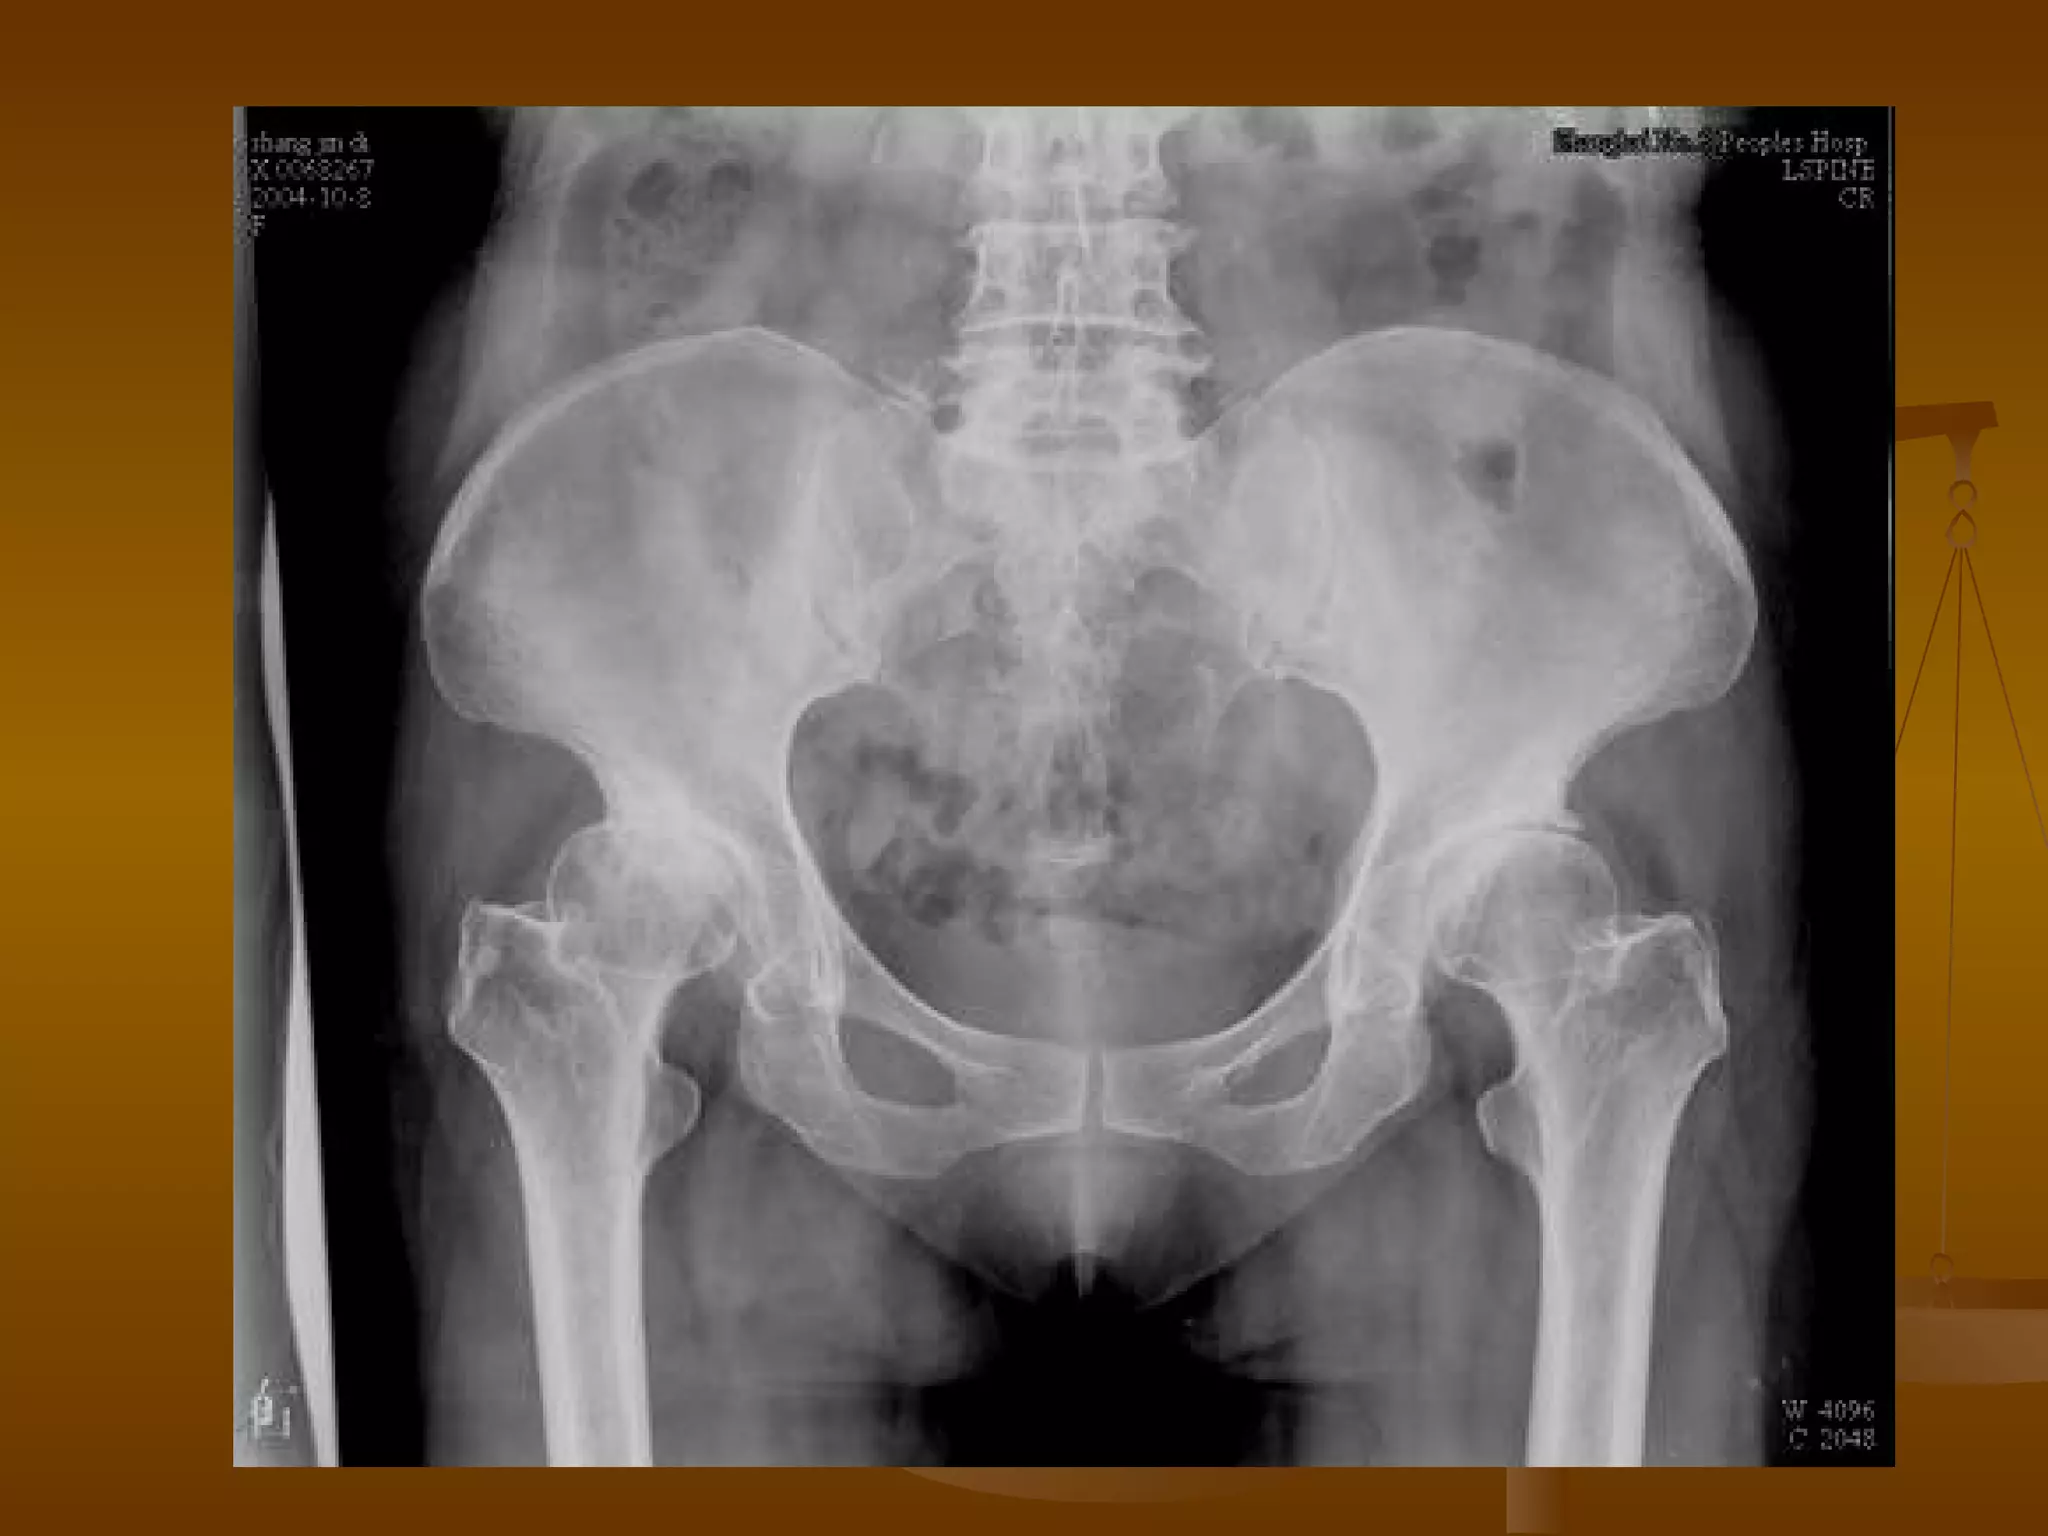

X 线诊断 X 光表现—早期 股骨头表面光整,无变形,髋关节间隙不狭窄,股骨头骨质无改变。 仅见股骨头弥漫性骨质稀疏,小梁模糊。 局限性骨密度增高、硬化,在骨密度增高区的边缘有斑片状密度减低区。 股骨头关节面皮质下出现星月形透亮区。病变常见于股骨头外上部负重区,病变范围多小于股骨头关节面 1/2 。

X 线诊断 X 光表现—中期 髋关节间隙不狭窄,股骨头轻度变形,出现轻度台阶征,股骨头尚未明显塌陷、碎裂。 股骨头密度不均匀,出现囊样或扇形骨质破坏区,周围可有高密度新骨增生。 病变常位于股骨头上部,累及范围多小于股骨头关节面 2/3 。

X 线诊断 X 光表现—晚期 股骨头明显变形、压缩、塌陷、骨密度不均匀。 病灶可累及整个股骨头,最终出现股头分节、碎裂。 并导致髋关节间隙狭窄和退行性骨关节炎。